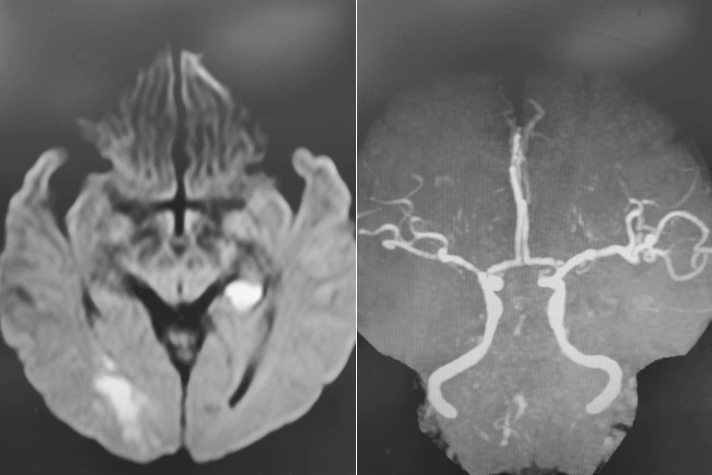

既往病史影像留存:

首次发病:

导丝怎么扩【载药时代 球扩天下】NOVA DES®颅内药物洗脱支架在椎动脉颅内段重度狭窄的应用二例_https://www.jmylbn.com_新闻资讯_第4张

DWI

导丝怎么扩【载药时代 球扩天下】NOVA DES®颅内药物洗脱支架在椎动脉颅内段重度狭窄的应用二例_https://www.jmylbn.com_新闻资讯_第5张

MRA

重要影像结论:后循环供血区多发梗死灶,后循环血管显影不良。